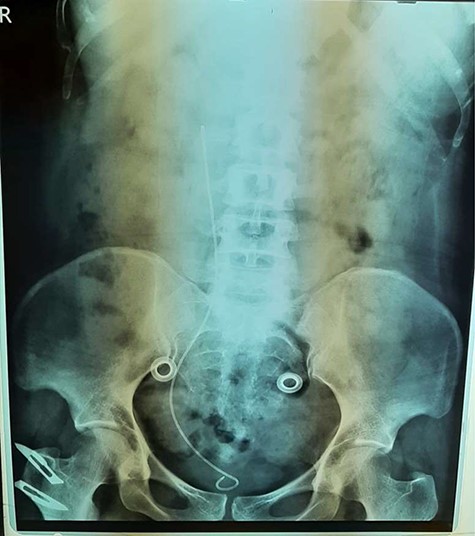

An abdominal ultrasonography revealed moderate right renal hydronephrosis and proximal hydroureter. A routine X-ray kidney-ureter-bladder (KUB) was normal. Intravenous urography (IVU) showed right renal hydronephrosis with delayed excretion and drainage (grade II) with s shape of the upper segment of the right ureter (Fig. 1). Then, the patient underwent right retrograde ureteroscopy with contrast to confirm the findings. Depending on these results, we decided to do the surgery for a right retrocaval ureter. After taking the patient consent, we had used Kocher approach to reach retroperitoneal space. After isolating of the right renal pelvis and ureter, the segment of retrocaval ureter was lower the ureteropelvic junction ~3 cm and dilated. We transected the pathological segment (~3 cm) of the ureter and then we did ureteropelvic end-to-end anastomosis. We inserted a double-j stent (Fig. 2). After a month, there was no hydronephrosis, and we removed the double-j stent. Six months follow-up demonstrates complete resolution of this pathology.

In the literature, retrocaval ureter has been classified into two clinical types, in accordance with the common radiological appearance. The more common type 1 (also named ‘low loop’) is characterized by the so-called ‘typical S’ or ‘fishhook’ deformity of the ureter to the level of the obstruction [3]. In this case, the abnormality was type 1 and the obstruction was at the right side beside the lateral margin of the IVC at the level of lumbar vertebrae L2–L3.

The imaging studies are important for an accurate preoperative diagnosis and successful surgical management. Abdominal ultrasound demonstrates hydronephrosis and proximal hydroureter without calculus. The IVU shows typical ‘fish hook’ or ‘J’- or ‘S’-shaped deformity in the proximal dilated ureter with moderate hydronephrosis. Nowadays, computed tomography urography is preferred over IVU or retrograde pyelography (RPG) as it may depict the anomaly in three dimensions giving the most ‘wholesome’ solution to its diagnosis [3]. For our patient, ultrasonography revealed moderate right renal hydronephrosis, and proximal hydroureter and the IVU showed right renal hydronephrosis with delayed excretion and drainage (grade II) with s shape of the upper segment of the right ureter, and we considered IVU result as a diagnosis.